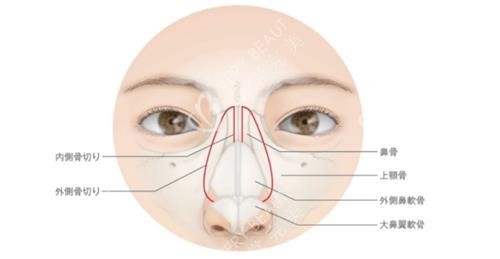

假体隆鼻是较为常见的隆鼻方式,常用的假体材料有硅胶和膨体。硅胶假体价格相对较为亲民,一般在3000 - 8000元左右。这是因为硅胶具有较好的弹性和稳定性,易于雕刻成型,手术操作相对简单,所以费用不会太高。而膨体材料质地更接近人体组织,术后结果更加自然,但价格也会偏高,通常在8000 - 15000元之间。膨体的微孔结构可以让人体组织长入,增加了固定性,但在雕刻和植入过程中难度稍大,这也导致了其收费相对较高。

肋骨鼻费用

肋骨鼻是取自身的肋软骨来塑造鼻型,由于采用的是自身材料,不会出现排异反应,结果也更加持久和自然。不过,取肋软骨的手术过程相对复杂,对医生的技术要求较高。肋骨鼻的收费一般在15000 - 30000元。其中包含了取肋软骨的手术费用、软骨雕刻费用以及隆鼻手术的费用等。